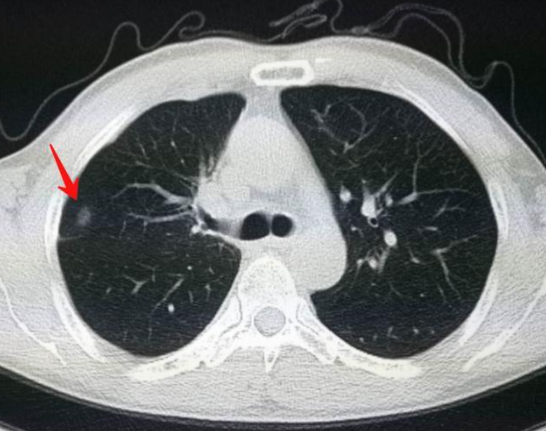

据估计,目前我国肺结节的患病率约在20%以上。肺结节虽然一般情况下都是属于良性的,但是如果不注意调控,也会导致病变的问题加重,危害身体健康,因此,一旦查出肺结节,一些错误的习惯要尽早改正!

肺结节出现,身体会有5个信号提醒你!

查出肺结节后,一般情况下医生不会作出治疗,只是建议根据结节大小和性质决定肺结节复查间隔时间。约为3-12个月一次。但是实际上我们也可以从食疗方面来进行肺结节的调理。